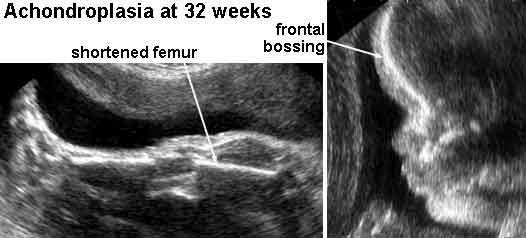

achondroplasia

Achondroplasia

When can rhyzomelia be diagnosed in utero?

by femur length

27 - 30 weeks

measurement of femur length starts dropping off

What is Achondroplasia?

very short limbs and sometimes a face that is small in relation to the skull